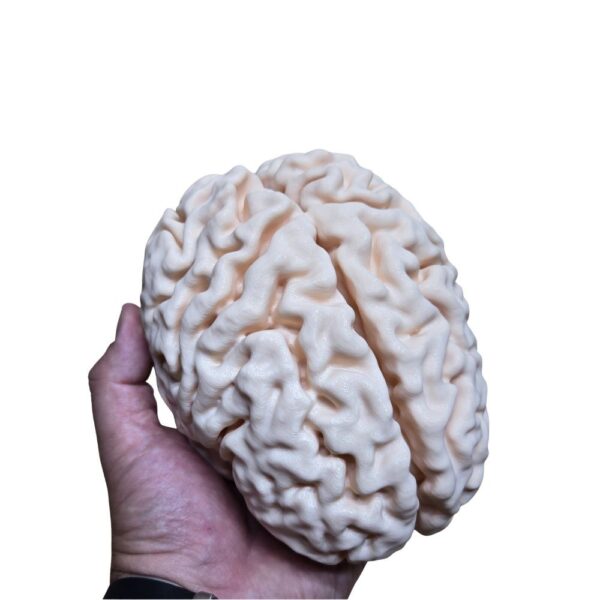

Obtenez une précision absolue avec cette réplique issue d’un scan 3D d’un véritable cerveau humain. Chaque circonvolution et structure est reproduite à l’identique de la réalité, offrant un outil d’étude et de référence d’un réalisme inégalé pour les passionnés et professionnels.

| Cerveau Humain Anatomique (Scan Réel) – Réplique Haute Fidélité | 1 11900 د.ج |